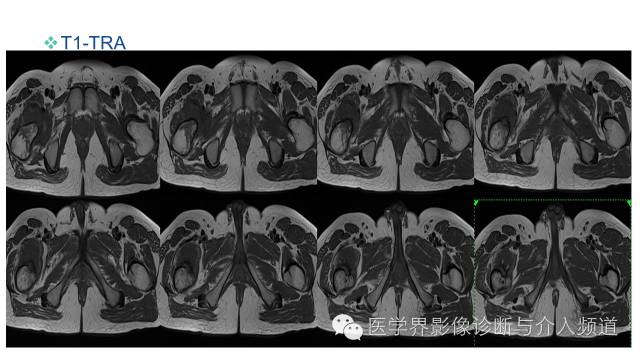

MR平扫及增强示:

右侧股骨上段见不规则形长T1短等T2异常信号,直径约1.5cm,邻近骨皮质破坏,其内骨髓可见斑片状长T1等长T2混杂信号,边界不清,股前方可见软组织肿块,呈长T1等长T2混杂信号,DWI呈明显高信号;注入GD-DTPA后,股骨内病灶呈轻度强化,周围软组织呈明显不均质强化。左侧髋关节诸组成骨对位关系可,未见明显骨质破坏征象,双侧髋关节可见少量斑片状长T2液体信号影。